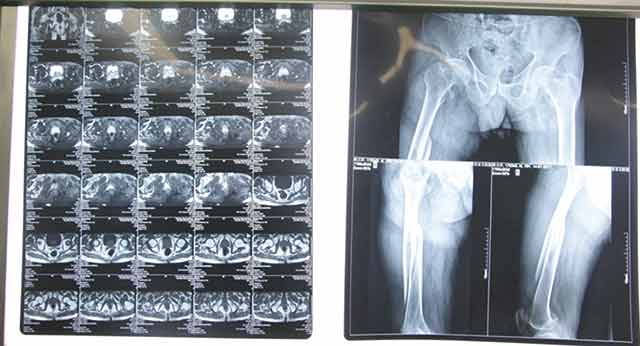

▲術(shù)前

經(jīng)過骨科專家團(tuán)隊(duì)的詳細(xì)查體以及相關(guān)拍片、CT等輔助檢查,韓大爺被診斷為右側(cè)的股骨干骨折合并同側(cè)粗隆間骨折。通過和病人及家屬耐心細(xì)致地溝通,韓大爺收住我院骨科。經(jīng)過詢問病史,了解到韓大爺有胃出血及疝修補(bǔ)手術(shù)史約10余年,并伴有老年高血壓病史,年事已高、病情復(fù)雜,需要制定更為詳細(xì)的診療方案。骨科主任楊連海及副主任孫守全立即組織科內(nèi)討論,充分與患者家屬進(jìn)行溝通、以得到家屬的認(rèn)可,細(xì)致而縝密地結(jié)合病人的個(gè)體情況定制手術(shù)方案。由于病情復(fù)雜,麻醉科主任修冬云在手術(shù)前親自看望韓大爺?shù)纳眢w狀況,認(rèn)真分析評(píng)估手術(shù)的風(fēng)險(xiǎn)程度,排除手術(shù)禁忌,選擇合適的麻醉方式。經(jīng)過積極的術(shù)前準(zhǔn)備,孫守全副主任擇期在硬膜外麻醉下完成了髖部骨折+同側(cè)股骨干骨折髓內(nèi)重建釘?shù)膬?nèi)固定手術(shù),手術(shù)過程非常順利,骨折復(fù)位基本達(dá)到解剖復(fù)位。術(shù)后經(jīng)過預(yù)防感染、鎮(zhèn)痛、預(yù)防下肢深靜脈血栓等治療,韓大爺恢復(fù)的非常好,沒有出現(xiàn)感染、血栓等并發(fā)癥,而且傷口甲級(jí)愈合。